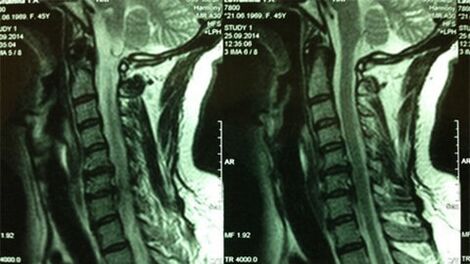

- X -Ray van de cervicale afdeling; In de eerste fase van het proces zal de MRI van de cervicale afdeling informatiefer zijn - het zal zorgen voor een hoge visualisatie van vaste en zachte weefsels - de toestand van de tussenwervelschijven, de aanwezigheid van osteofyten, vervormingen, schade aan de zenuwwortels en bloedvaten; zal de toestand van de ligamenten, spieren, botweefsel evalueren;